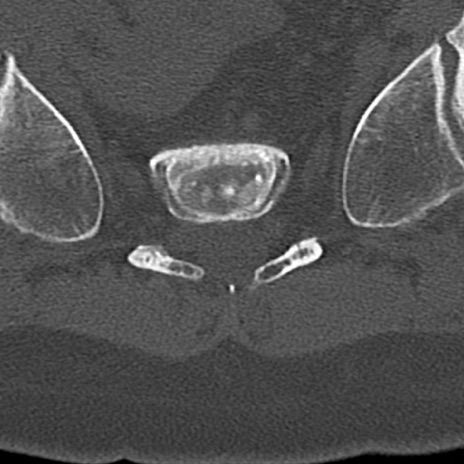

【整形】TIPS症例4 腰椎CT(横断像)

腰椎CT

横断像と矢状断像